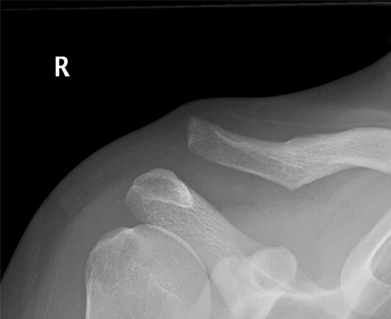

The two most common symptoms of AC joint injury include pain and visual deformity of the shoulder (Figure 1). Pain is usually located directly over the AC joint with both tenderness to palpation and shoulder movement. Depending on the severity of injury, the shoulder can appear similar to the other side or can have abnormal contouring.

Figure 1